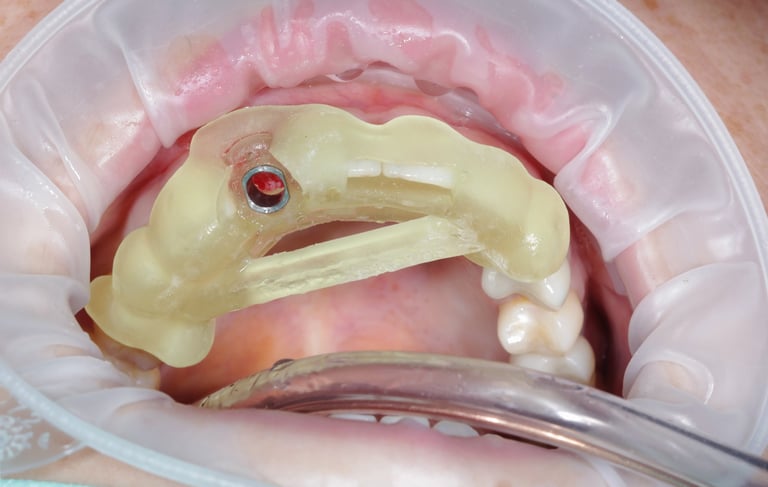

Consiste en exponer los implantes después de su integración ósea y colocar los pilares que servirán de soporte para las prótesis definitivas.

Cirugía de Conexión de implantes

Colocación de un pilar provisional para mantener el espacio y la estética mientras se espera la fabricación de la prótesis definitiva.

Colocación de Pilar de Cicatrización